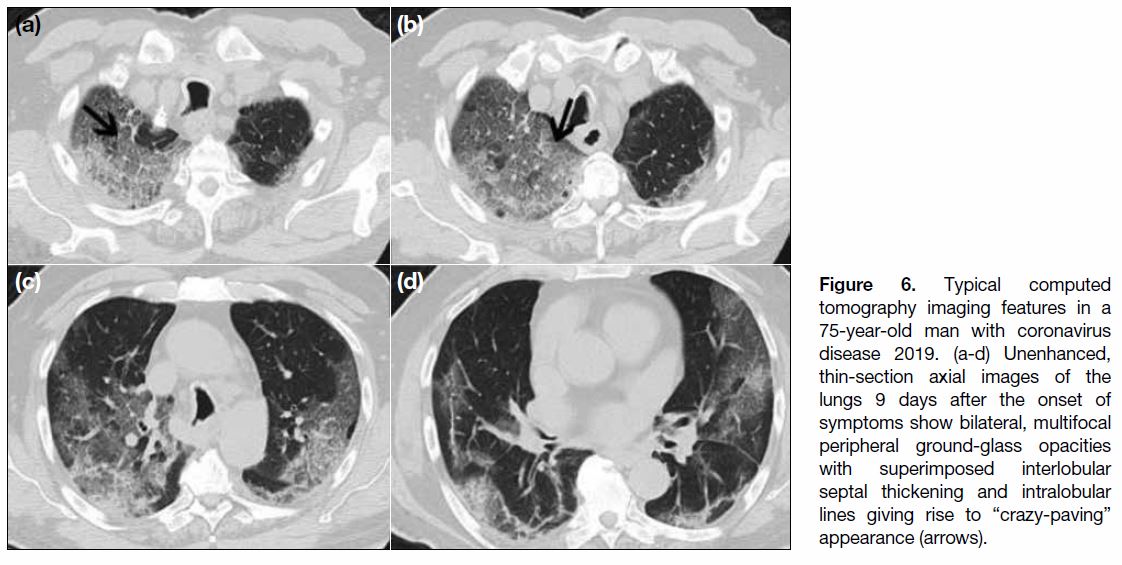

Imaging Features on Chest Computed Tomography

The cardinal hallmark of COVID-19 pneumonia on

chest CT is bilateral GGOs with or without consolidation

in peripheral and posterior lungs (Figures 3 and 4).[11] [21]

The GGOs often have rounded morphology (Figure 5)

or are present with interlobular septal thickening and

intralobular lines creating a “crazy-paving” pattern

(Figure 6).[20] GGO together with small areas of

consolidation may suggest an organising pneumonia

pattern of lung injury.[21]

Figure 6. Typical computed tomography imaging features in a 75-year-old man with coronavirus disease 2019. (a-d) Unenhanced, thin-section axial images of the lungs 9 days after the onset of symptoms show bilateral, multifocal peripheral ground-glass opacities with superimposed interlobular septal thickening and intralobular lines giving rise to “crazy-paving” appearance (arrows).

radiological findings, GGO (Figures 3 4 5 6 7) was the most

common, occurring in 95 (97.9%) patients. Consolidation

(Figure 4) was recorded in 57 (58.8%) patients, septal thickening in 28 (28.9%) patients, and reticular/linear densities in 18 (18.6%) patients. Bronchial wall

thickening and dilatation (Figure 4) were less common,